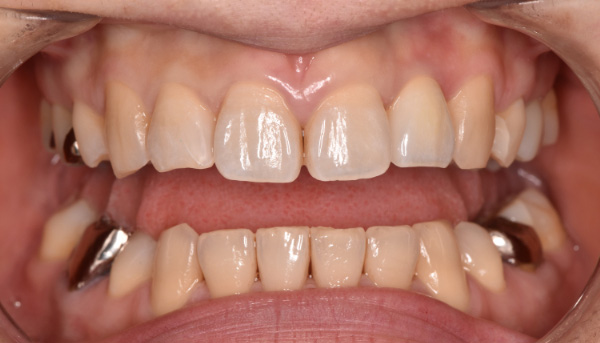

前歯のインプラント症例

「ブリッジの見た目が悪いので、キレイにしたい」

治療前

治療後

| 主訴 | ブリッジの見た目が悪いので、キレイにしたい |

|---|---|

| 治療期間 | 約4〜5ヶ月 |

| 治療費 | 1本あたり550,000円(税別) |

| 治療内容 | 前歯のインプラント治療 |

| 治療のリスク | 前歯のインプラント治療では、審美性の問題や骨密度不足によるインプラントの不安定、神経損傷や感染のリスクがあり、術後の腫れや痛みも発生する可能性があります。 |